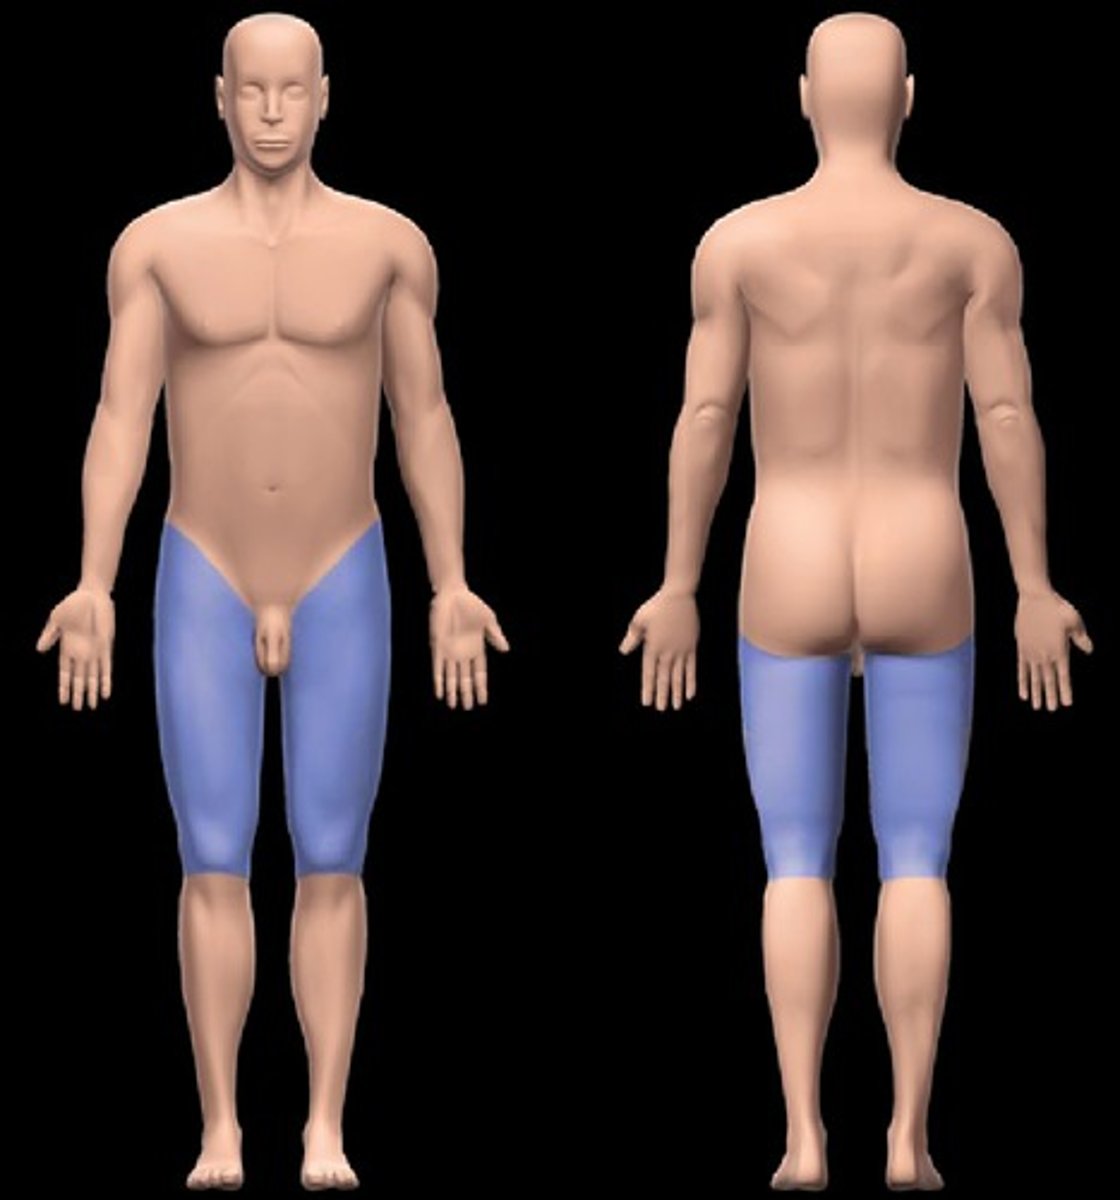

Femoral

Pertaining to the thigh

Inguinal

Groin area

Patellar

Front of knee

Popliteal

Back of knee